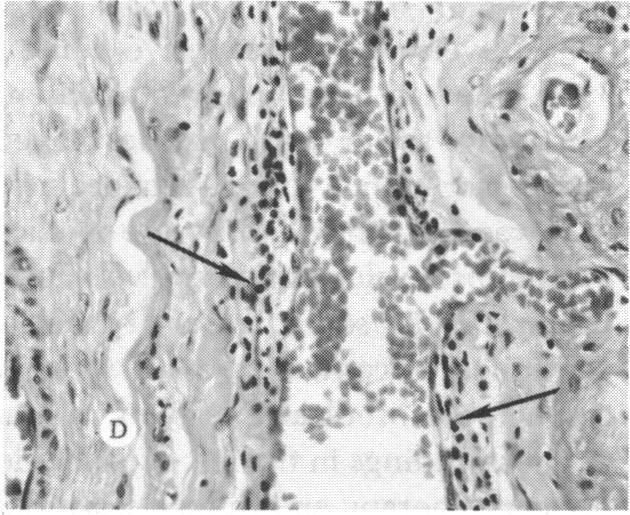

The clinical and histopathologic features of 29 eyes from 29 patients with central retinal vein occlusion (CRVO) are reported. A fresh or a recanalized thrombus was observed in each eye. This study considers the temporal aspects of the cases, and it notes the different morphologic features of the occlusion. These observations explain most of the variability of the changes observed in previous reports. We believe that these different features represent the various stages in the natural evolution of such a thrombus. The interval between CRVO and histopathologic study in our series ranged from six hours to more than 10 years. Local and systemic factors were reviewed and were found to be important in the pathogenesis of thrombus formation. Local diseases with a predisposing effect on CRVO included: glaucoma, papilledema, subdural hemorrhage, optic nerve hemorrhage, and drusen of the optic nerve head. Associated systemic diseases included: hypertension, cardiovascular and cerebrovascular disease, diabetes mellitus, and leukemia with thrombocytopenia. A fresh thrombus in the CRVO was observed in three (10.3%), and a recanalized thrombus in 26 eyes (89.7%). Endothelial-cell proliferation was a conspicuous feature in 14 (48.3%) of the eyes. Chronic inflammation in the area of the thrombus, and/or vein wall or perivenular area was observed in 14 (48.3%) of the eyes. Arterial occlusive disease was observed in seven eyes (24.6%). Cystoid macular edema was found in 26 (89.7%) of the eyes.

报告了29例视网膜中央静脉阻塞(CRVO)患者29只眼的临床和组织病理学特征。每只眼中均观察到新鲜或再通的血栓。本研究考虑了病例的时间因素,并记录了阻塞的不同形态学特征。这些观察结果解释了先前报告中观察到的变化的大部分变异性。我们认为这些不同特征代表了此类血栓自然演变的各个阶段。我们系列中CRVO与组织病理学研究之间的间隔时间从6小时到10多年不等。对局部和全身因素进行了回顾,发现它们在血栓形成的发病机制中很重要。对CRVO有 predisposing 作用的局部疾病包括:青光眼、视乳头水肿、硬膜下出血、视神经出血和视神经乳头玻璃膜疣。相关的全身疾病包括:高血压、心血管和脑血管疾病、糖尿病以及伴有血小板减少的白血病。在CRVO中观察到3只眼(10.3%)有新鲜血栓,26只眼(89.7%)有再通血栓。14只眼(48.3%)中内皮细胞增殖是一个显著特征。14只眼(48.3%)中观察到血栓区域、和/或静脉壁或静脉周围区域有慢性炎症。7只眼(24.6%)中观察到动脉闭塞性疾病。26只眼(89.7%)中发现黄斑囊样水肿。 (注:文中“predisposing”可能是“易患的”意思,但在专业医学语境中,可能有更准确特定含义,这里按常见理解翻译,具体含义需结合医学专业知识进一步确认。)